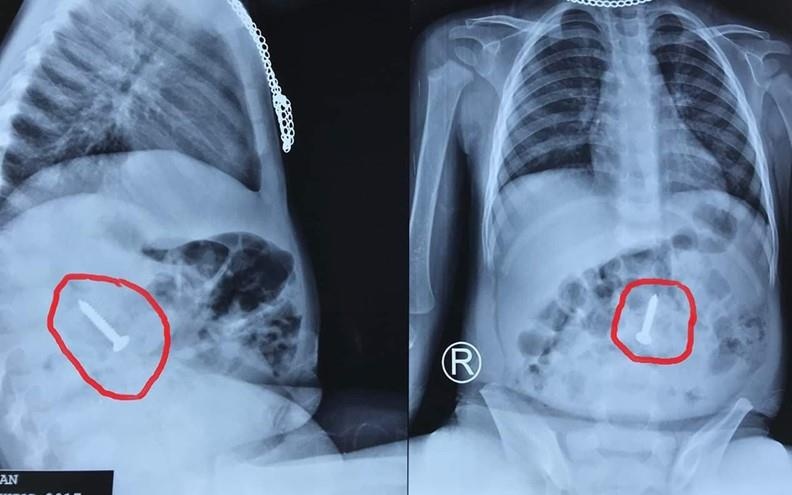

Trước đó, ngày 14/6, bệnh viện này tiếp nhận bệnh nhi N.H.H. (20 tháng tuổi) với chẩn đoán nuốt phải dị vật kim khí. Kết quả nội soi cho thấy tại đoạn cuối tá tràng của bệnh nhi có hình ảnh dị vật kim loại một đầu sắc nhọn (ốc vít kim loại) dài 3,5 cm.

| Hình ảnh chụp X-quang cho thấy chiếc đinh vít sắc nhọn ở trong cơ thể bệnh nhi. Ảnh: VOV. |